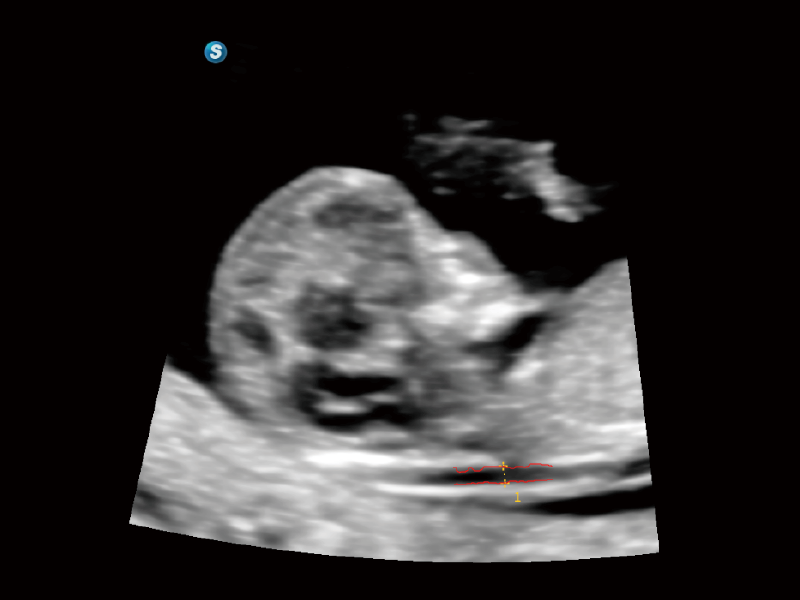

作为开立医疗全新打造的超高端旗舰超声产品,从探头抬起唤醒开启扫查到多维探头发射接收,通过先进的场成像发射、自适应聚合重建等技术,基于RF Data原始射频数据在图像生成、高端功能等方面实现突破,为妇产科、儿科提供全方位临床解决方案。

梦溪®P80以“关爱女性”为基石,提供全方位的解决方案,量身定制以满足女性的健康需求,涵盖妇科、生殖健康检查、产前筛查及产后康复等领域。